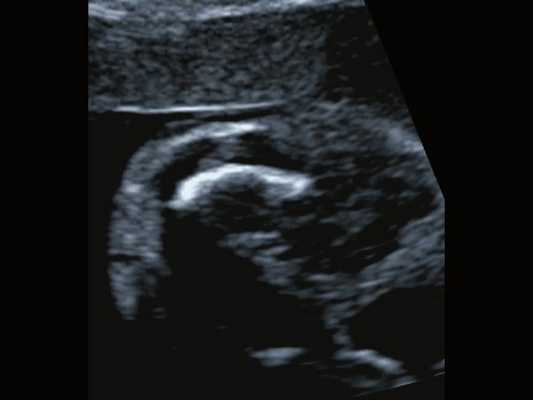

С каким трепетом каждая беременная ждет очередного ультразвукового исследования! Она хочет увидеть малыша, узнать, хорошо ли ему в утробе, разглядеть ручки и ножки, посмотреть, бьется ли сердечко. Но ожидание чуда часто не оправдывается. Во время исследования будущая мама видит экран с черно-белыми точечками и палочками, а в конце исследования - заключение на бумаге с непонятными цифрами и фразами. Давайте разберемся, что же написано в этом заключении.

Состояние плода

Во время первого исследования определяют, где расположен плод, исключая таким образом внематочное расположение плодного яйца. Позднее определяют положение плода в матке - головное или тазовое.

Уже начиная с первого исследования можно определить сердцебиения плода. В документации записывают наличие сердцебиения (с/б +), ЧСС - число сердечных сокращений (в норме ЧСС составляет 120-160 ударов в минуту). Отклонение показателей ЧСС при первом исследовании - увеличение или уменьшение числа сердечных сокращений - может служить признаком того, что у недавно зародившегося плода имеется порок сердца. Позднее, во 2 и 3 триместре, есть возможность подробно, детально различить и изучить сердечные клапаны и камеры. Изменение числа сердечных сокращений во 2 и 3 триместре может говорить о страдании плода, нехватке кислорода и питательных веществ.

Размеры плода

Сокращения, которые можно встретить в протоколах ультразвукового исследования, имеют следующие значения.

В 1 триместре беременности определяют диаметр плодного яйца (ДПР), копчико-теменной размер плода (КТР), то есть размер от темени до копчика. Измеряют также размеры матки. Эти измерения позволяют в 1 триместре достаточно точно судить о сроке беременности, так как в это время размеры плода наиболее стандартны. Относительно определения срока беременности по размерам плода и плодного яйца есть небольшой нюанс. В заключении могут записать не акушерский срок, считающийся от первого дня последней менструации, согласно которому беременность длиться 40 недель, а срок беременности от зачатия - эмбриональный срок. Срок беременности от зачатия на 2 недели меньше, чем акушерский срок. Однако если будущая мама сравнит результаты УЗИ и результаты осмотра, у нее может возникнуть недоумение, т. к. срок беременности по разным данным может расходиться на 2 недели. Уточнив у своего доктора, какой срок указан в заключение первого УЗИ, вы разрешите свои сомнения.

При последующих исследованиях, во 2 и 3 триместрах беременности, определяют следующие показатели развития плода:

- - бипариетальный размер - размер между височными костями, - лобно-затылочный размер,

- ОГ - окружность головки,

- ОЖ - окружность живота.

Также измеряют длину бедренной кости, плечевой кости, возможно измерение более мелких костей предплечья и голени.